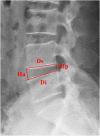

Methods: We included 285 patients with single-segment lumbar disc herniation treated using transforaminal endoscopy lumbar discectomy TELD from January 2017 to December 2019 at the First Affiliated Hospital of the University of South China. Patients were classified into early recurrence and non-early recurrence groups based on clinical symptoms and MRI reexamination. Imaging data (eg, disc height index (DHI), Pfirrman grades, base width, postoperative annulus-fibrosus tear size, cross-sectional area of the foramen (CSAF), etc.)were analyzed, and multivariate, binomial logistic regression was utilized to determine which factors were associated with early recurrence after TELD.

Results: A total of 285 patients completed surgery and clinical follow-up, during which 19 patients relapsed within 6 months postsurgery, for an early recurrence rate of 6.7%. There were statistically significant differences between DHI, Pfirrman grades, base width, postoperative annulus-fibrosus tear size, herniation sites, CSAF and Modic changes between the early recurrence and non-early recurrence groups (P < .05). On multivariate logistic regression,the degree of disc degeneration (OR = .747, P = .037), CSAF (OR = 5.255, P = .006), degree of Modic change (OR = 1.831, P = .018) and base width of the herniation (OR = 4.942, P = .003) were significantly correlated with early recurrence after TELD.

Conclusions: Postoperative annulus-fibrosus tear size, DHI, and location of the disc herniation were associated with early recurrence after TELD. Increased base width of the herniation, severe disc degeneration, decreased CSAF and Modic change were risk factors for early recurrence after TELD.